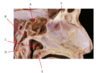

Which nerve is labeled by F?

Posterior superior alveolar nerve

(Branch of CN V2)

A.

B. Chorda Tympani (branch of CN 7)

C. Inferior Alveolar n. (branch of CN 5.3)

D. Facial n. (CN 7)

E. Lingual n. (branch of CN 5.3)

F. Posterior Superior Alveolar n. (branch of CN 5.2)

G.

H. Infraorbital n. (branch of CN 5.2)

I. Mental n. (branch of CN 5.3)

What is the carina?